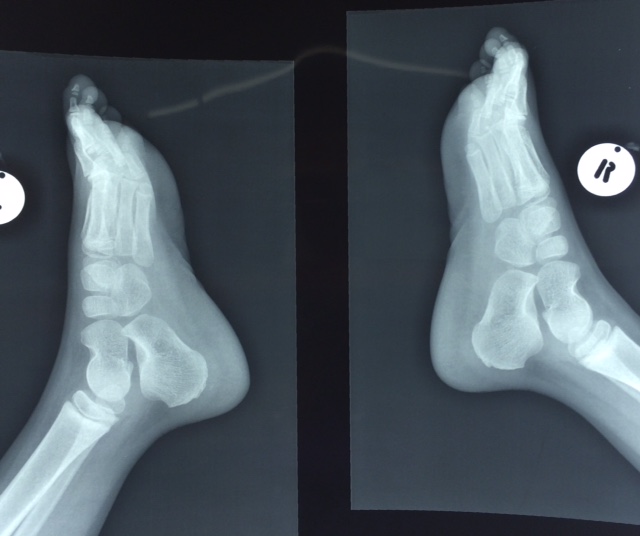

Нужен совет:

Противоречивый опыт в разных источниках- какой палец удалять?

Медиальный? Повреждение капсулы может в последующем привести к отклонению большого пальца (????).

Если латеральный - то страдает межпальцевой  промежуток, и может развиться варусная деформация (я пока не видел, может, короткий срок наблюдения - 2, может 3 года).

Всё-таки, наверное, лучше удалить латеральные пальцы с коррекцией и фиксацией спицами.

Ребёнку 4 года.